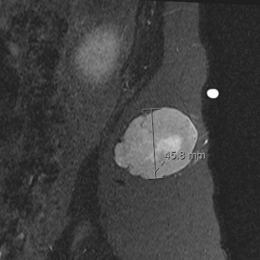

Round Cell Liposarcoma is a malignant, or cancerous, soft-tissue sarcoma that most commonly occurs in the deep tissues of the thigh, or other extremities. It is fairly aggressive and has a greater potential for metastasis.